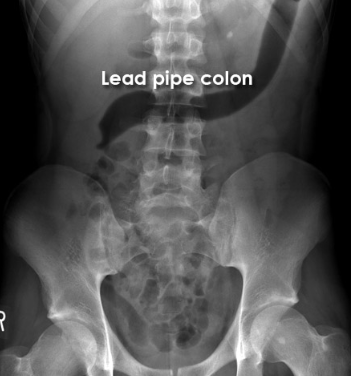

Lead pipe colon

This patient with ulcerative colitis has a featureless segment of transverse colon with loss of the normal haustral markings.

This ‘lead pipe’ appearance is associated with longstanding ulcerative colitis.